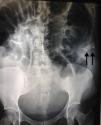

Abdominal X-rays (Figs. 1 and 2) showed significant distension of the intestinal loops, interloop oedema, absence of gas in the rectal ampulla, fluid-air levels and the image of a foreign body in the upper left quadrant.

Given the above, a diagnosis of intestinal occlusion secondary to a foreign body was made, and therefore an exploratory laparotomy was performed. The procedure was reported complication-free, finding a piece of textile lodged in the upper left quadrant, hardened and adhering to the intestinal loops, with friable, oedematous surrounding tissue, and peritoneal reaction fluid estimated to be approximately 100ml.